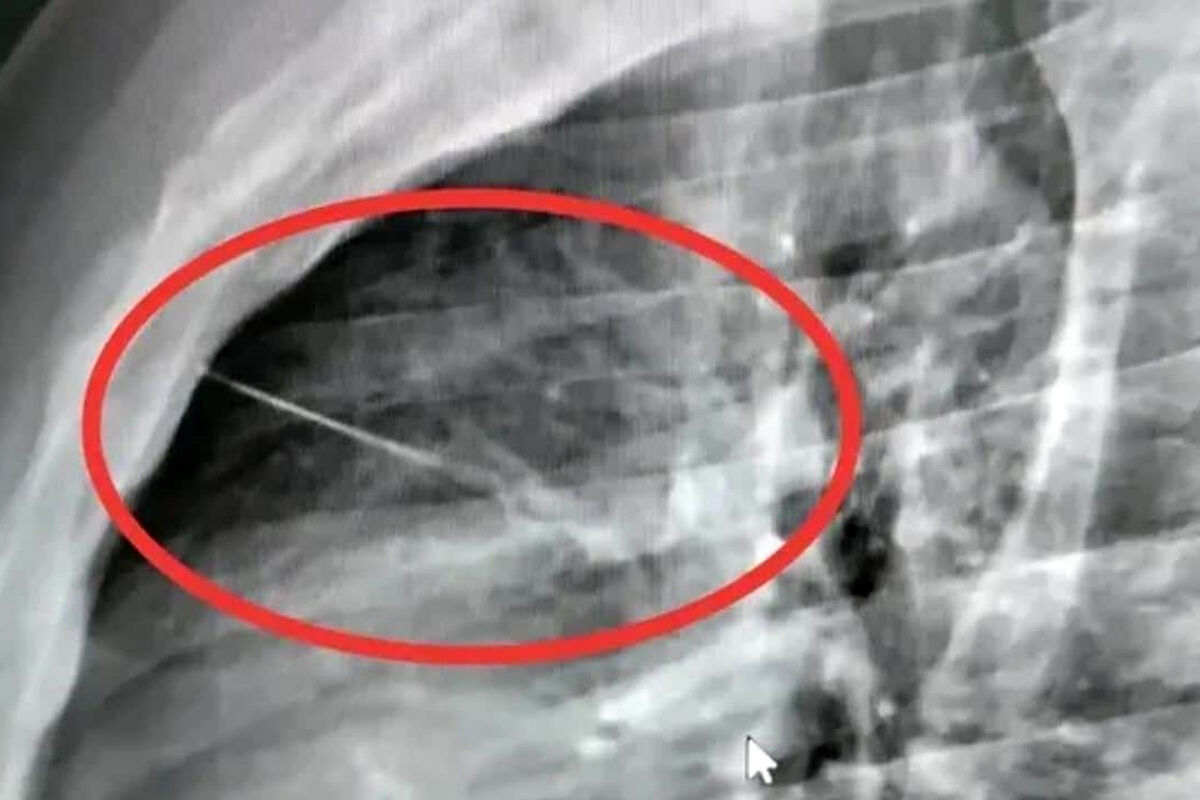

Пациентка вовремя обратилась за помощью, и бригада скорой доставила ее в стационар. Рентген брюшной полости показал инородное тело в желудке. Врачи первого хирургического отделения подготовили ее к экстренной операции, после чего с помощью современного оборудования эндоскописты аккуратно удалили опасный предмет, не допустив осложнений.